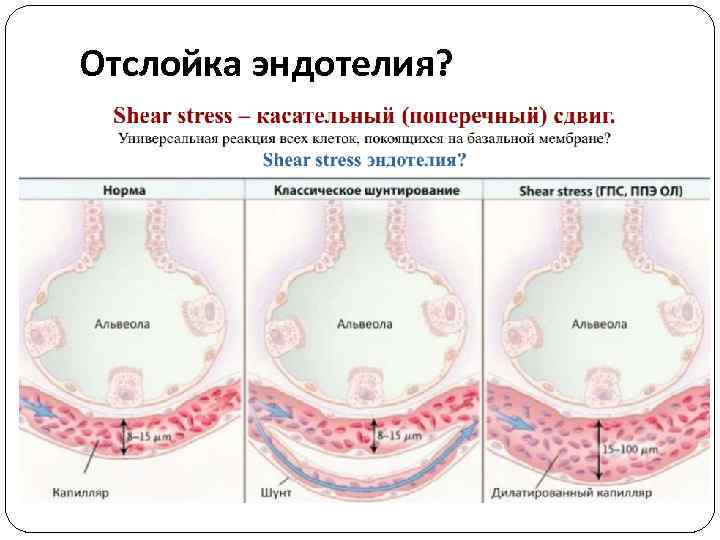

Механизмы Основные механизмы : • Рост гидростатического давления (легочные вены и капилляры) • Проницаемость эндотелия • Персистирующая легочная вазодилатация – “shear stress” – отслойка эндотелия • Реперфузия (интенсивная терапия шока) или избыточная инфузия

Механизмы Основные механизмы : • Рост гидростатического давления (легочные вены и капилляры) • Проницаемость эндотелия • Персистирующая легочная вазодилатация – “shear stress” – отслойка эндотелия • Реперфузия (интенсивная терапия шока) или избыточная инфузия

Отслойка эндотелия?

Отслойка эндотелия?